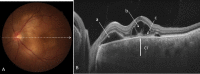

Swept source optical coherence tomography (SS-OCT) was introduced in clinical practice in 2012. Because of its deeper penetration and faster acquisition time, SS-OCT has the ability to visualize choroid, vitreous, and retinal structures behind dense preretinal hemorrhages. Swept source optical coherence tomography has positively influenced and hugely contributed to the research of the vitreous body. It is the first ophthalmic diagnostic technology to demonstrate the entire structure of the posterior precortical vitreous pocket (PPVP) in vivo. The roles of the PPVP in physiological posterior vitreous detachment and vitreoretinal interface disorders have now been elucidated. The presence of a connecting channel between the PPVP and Cloquet's canal suggests that the aqueous humor drains into the premacular space. Deeper penetration of SS-OCT has made it possible to view the choroid. It also has an important role in central serous chorioretinopathy and uveitis. We have also been able to treat Harada disease by monitoring the choroidal thickness by SS-OCT.